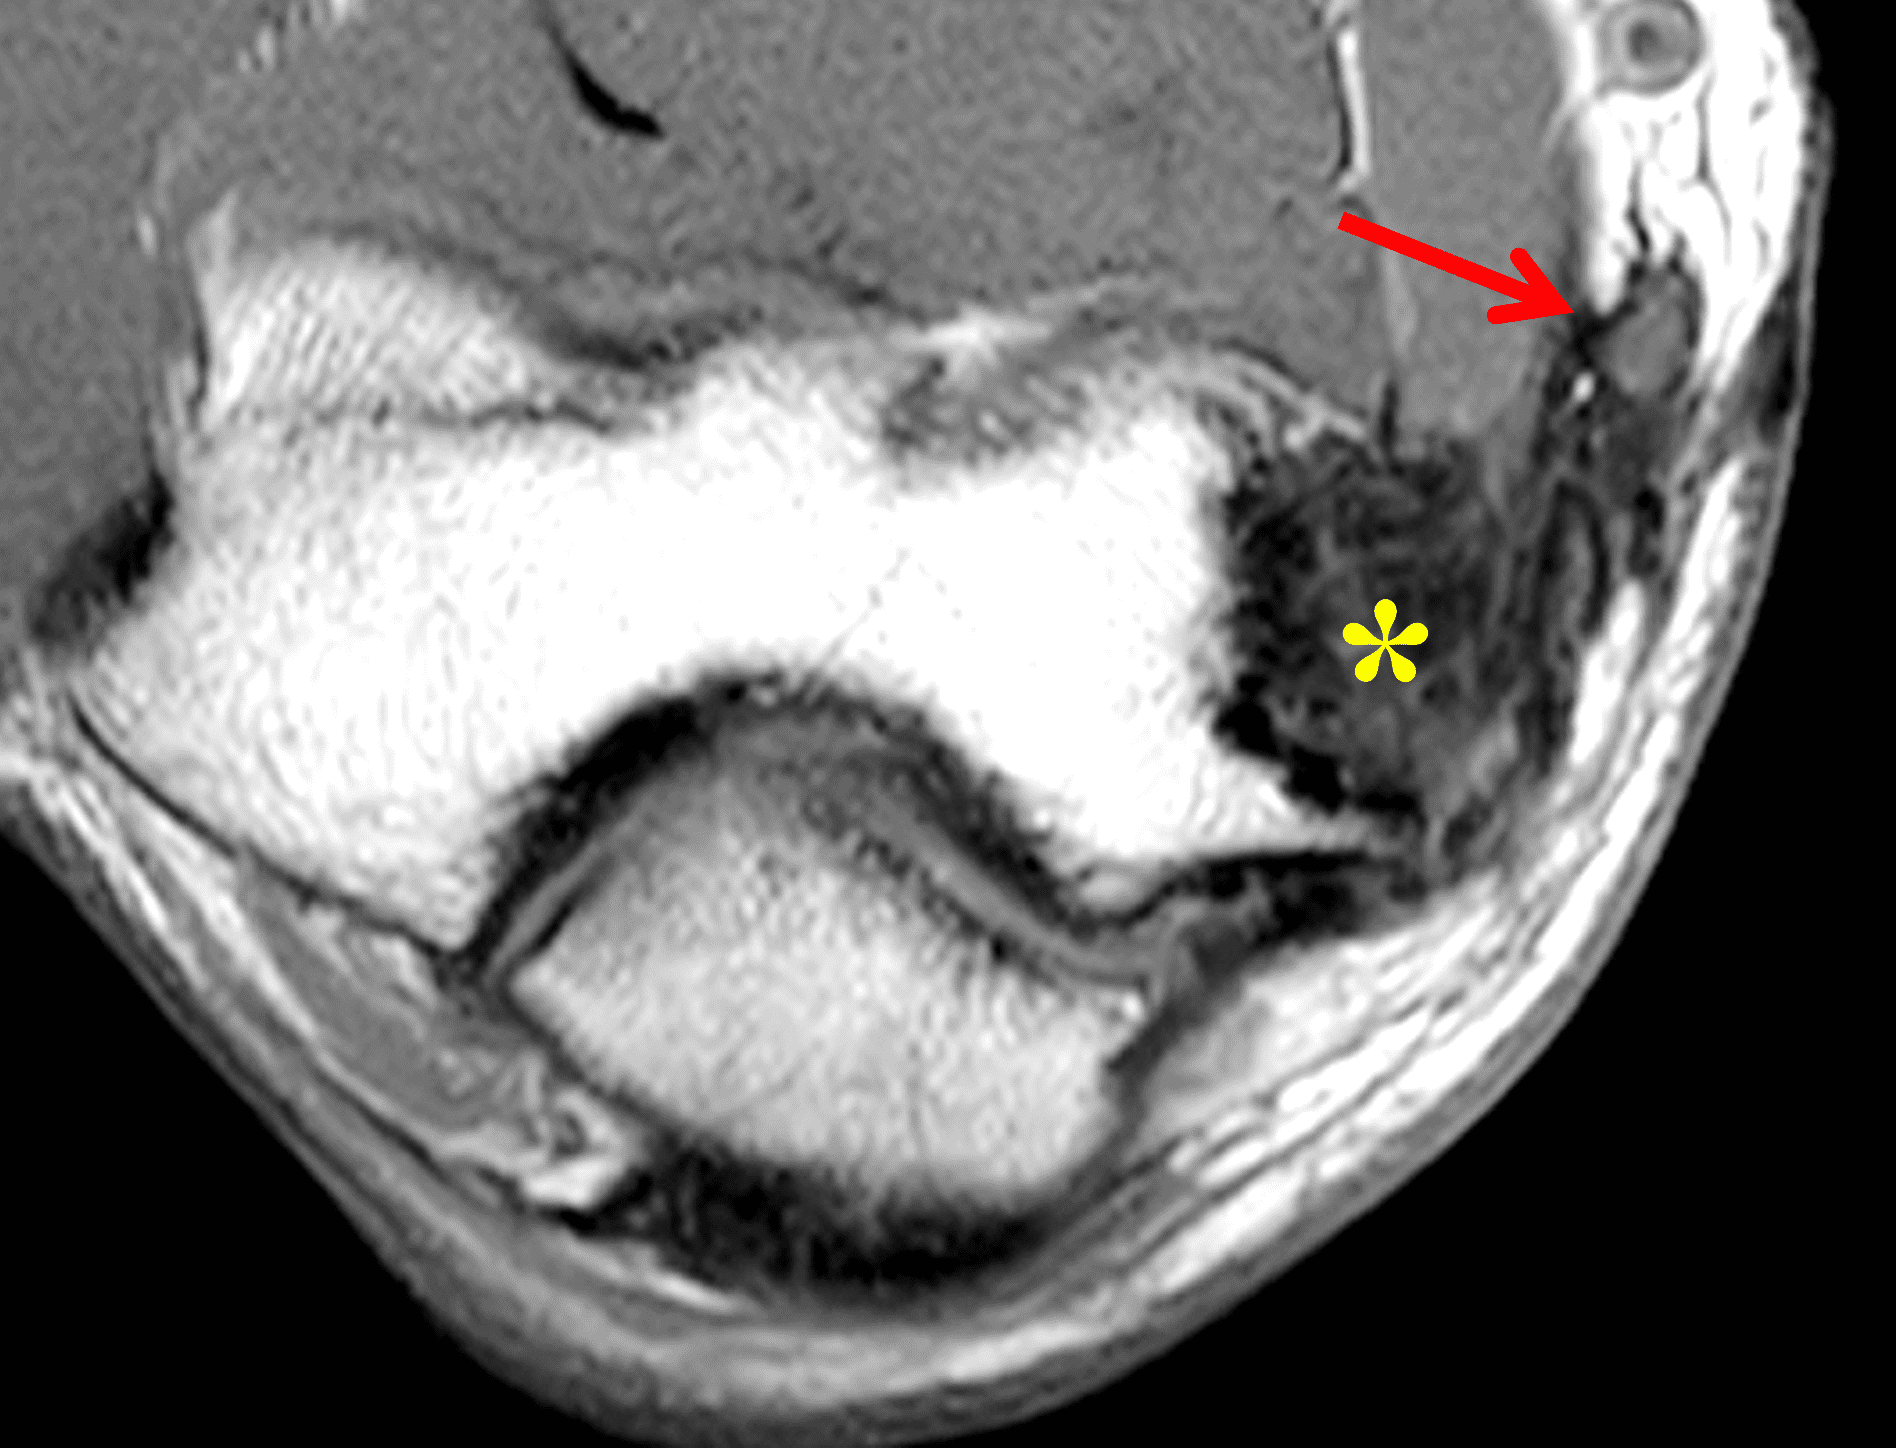

A 55-year-old man complains of pain, numbness, and tingling in the ulnar aspect of the hand and in the small and ring fingers. The symptoms are more severe with elbow flexion and during sleep. He has no muscle weakness or history of trauma. Axial T1-weighted (1A, 1B) and fat-suppressed, fluid-sensitive (1C, 1D) images are shown. What are the findings? What is your diagnosis?

Figure 2: At the level of the cubital tunnel (2A and 2C), identifiable by the thin cubital tunnel retinaculum (yellow arrow), the ulnar nerve (red arrow) is focally enlarged and hyperintense compared to the nerve more distally (2B and 2D), where it lies between the two heads of the flexor carpi ulnaris muscle (asterisks). No soft tissue mass is present.